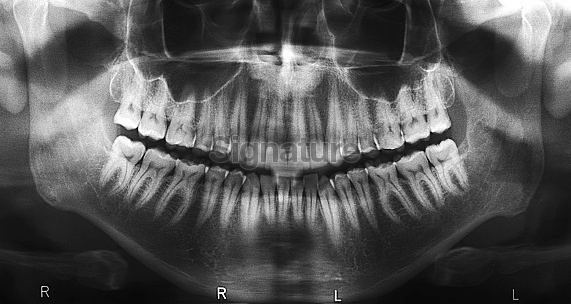

그러다 이거 괜찮겠다 싶어 생각해간 주제가 치과 X-ray 사진을 학습해 치아 질병을 감지하는 모델이었다.

이미지 형태도 획일화돼있지, 해야할 작업도 단순하지, 실용성 있지... 생각만 했을때 진짜 좋은 아이디어같아서 나름 자신있게 들고갔다.

지금 생각해보면 그 때 당시의 한참 모자란 검색 능력때문에 그냥 2주를 날린 것 같다.. 5년전에 생각했으면 좋았을 것 같다는 피드백을 듣고 제대로 찾아보니 훌륭한 성능의 모델을 만든 논문이 여럿 나왔다. 진작 검색해보고 아이디어를 좀 걸러냈어야 했는데..